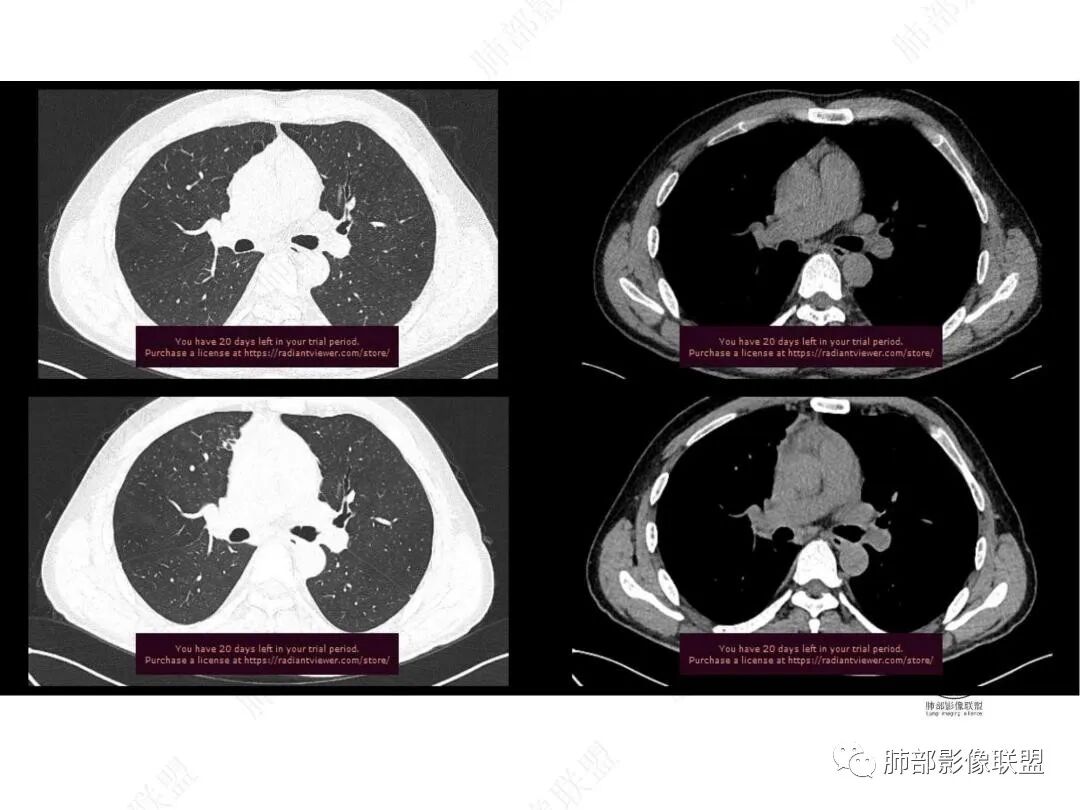

平扫图像

增强图像

中年男性,反复低热3月伴近期乏力及右上腹隐痛,白细胞,中性粒及淀粉样蛋白A增高,PCT不高,IGA、IGg增高,类风湿因子增高,未提供IGg4水平,影像改变,左侧肋骨陈旧性骨折(2020年已存在)右上叶前段胸骨旁的胸膜下新发病灶,支气管进入后一段才堵塞,肺动脉进入,走行自然,未见破坏,明显均匀强化,气管及支气管壁有增厚,钙化,纵隔内淋巴结增大,均匀强化,无坏死,纵隔内脂肪混浊,局部强化,肝内低密度灶,延迟强化(肺内病灶,淋巴结、混浊脂肪,肝内病灶强化均一致,且均为延迟强化)。初步考虑:免疫相关性炎症,IGg4相关炎症可能大,依据:IGA、IGg增高(未提供IGg4,可能是故意隐藏了),类风湿因子增高,炎性指标增高,但PCT不高,细菌感染可能就变小,加上病变同时累及肺、纵隔淋巴结,纵隔内脂肪、肝。

2020.12-2022.02右上肺新发实性病灶,边缘可见刀切征,局部边缘模糊可见絮状影及少许树芽征,邻近胸膜牵拉,增强后渐进性强化,欠均匀。考虑1.炎性病变可能大,结合左上肺胸膜处陈旧性病灶,右肺病灶考虑结核可能;2.肿块型病灶 渐进性强化,考虑炎性肌纤维母细胞瘤。3.结合肝右后叶低密度灶,增强后渐进性强化,延时期与肝脏密度相似,局灶性肝炎性改变?加IgG增高 血沉明显升高 自身免疫相关病变?建议CT下穿刺活检扫描及进一步实验室检查IG4等

右上叶前段胸膜下新发病灶;纵隔淋巴结较前增大

边缘平直,有锯齿状影

支气管进入其中,中近端堵

远端见斑片状高密度影

强化与肌肉类似,纵隔淋巴结强化类似

与胸膜关系:糊墙

1.中年男性,临床发热,症状较轻,中长病程,炎性指标轻度增高。

2.右肺上叶纵隔旁新发实性密度病灶,密度均匀,轻度强化,未见空洞、液化坏死及钙化,血管穿行自如,支气管进入后狭窄截止。灶周磨玻璃影边界不清,病灶未见明显分叶毛刺,平直、轻度收缩、周围偶见结节影,但未见树芽征。注意纵隔胸膜侵入或突入比较明确。纵隔淋巴结轻度增大。

3.右肺容易想到的病变有慢性炎症、IGg4相关、新生物(炎性肌纤维母细胞瘤、腺癌等)。但病灶侵入纵隔胸膜应当更符合恶性肿瘤。病程进展及强化等影像特点不支持继发性肺结核。

4.肝脏病灶没有假包膜,没有动脉早期强化,没有肝硬化,未见扩张胆管,未见环形强化,也未显示靶征,缺乏肝细胞肝癌、胆管细胞癌、转移癌或肝脓肿特征。